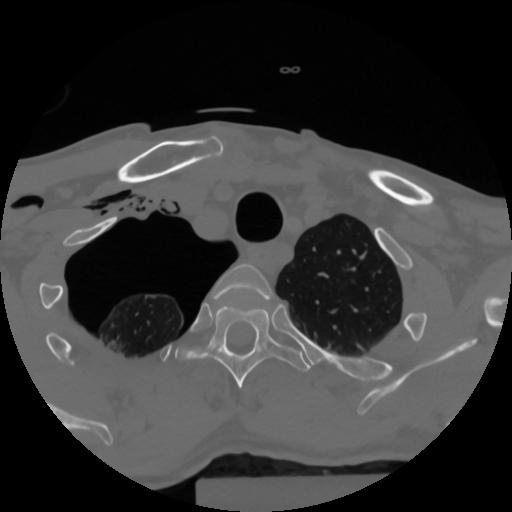

12 P.BLANDAS,,Vol,0.5,P.BLANDAS,,